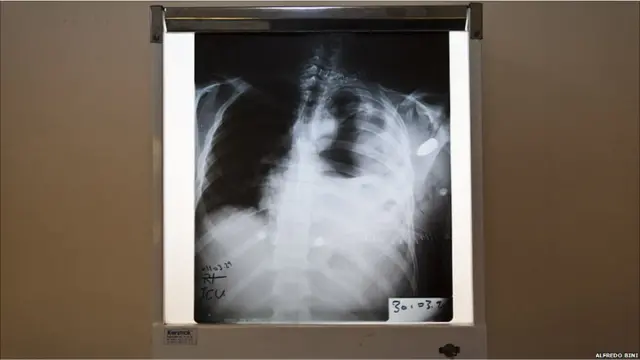

Keterangan gambar, Foto rontgen ini memperlihatkan pecahan peluru di dada seorang pengacara sejak 10 hari lalu, hingga kini dia dalam keadaan koma.